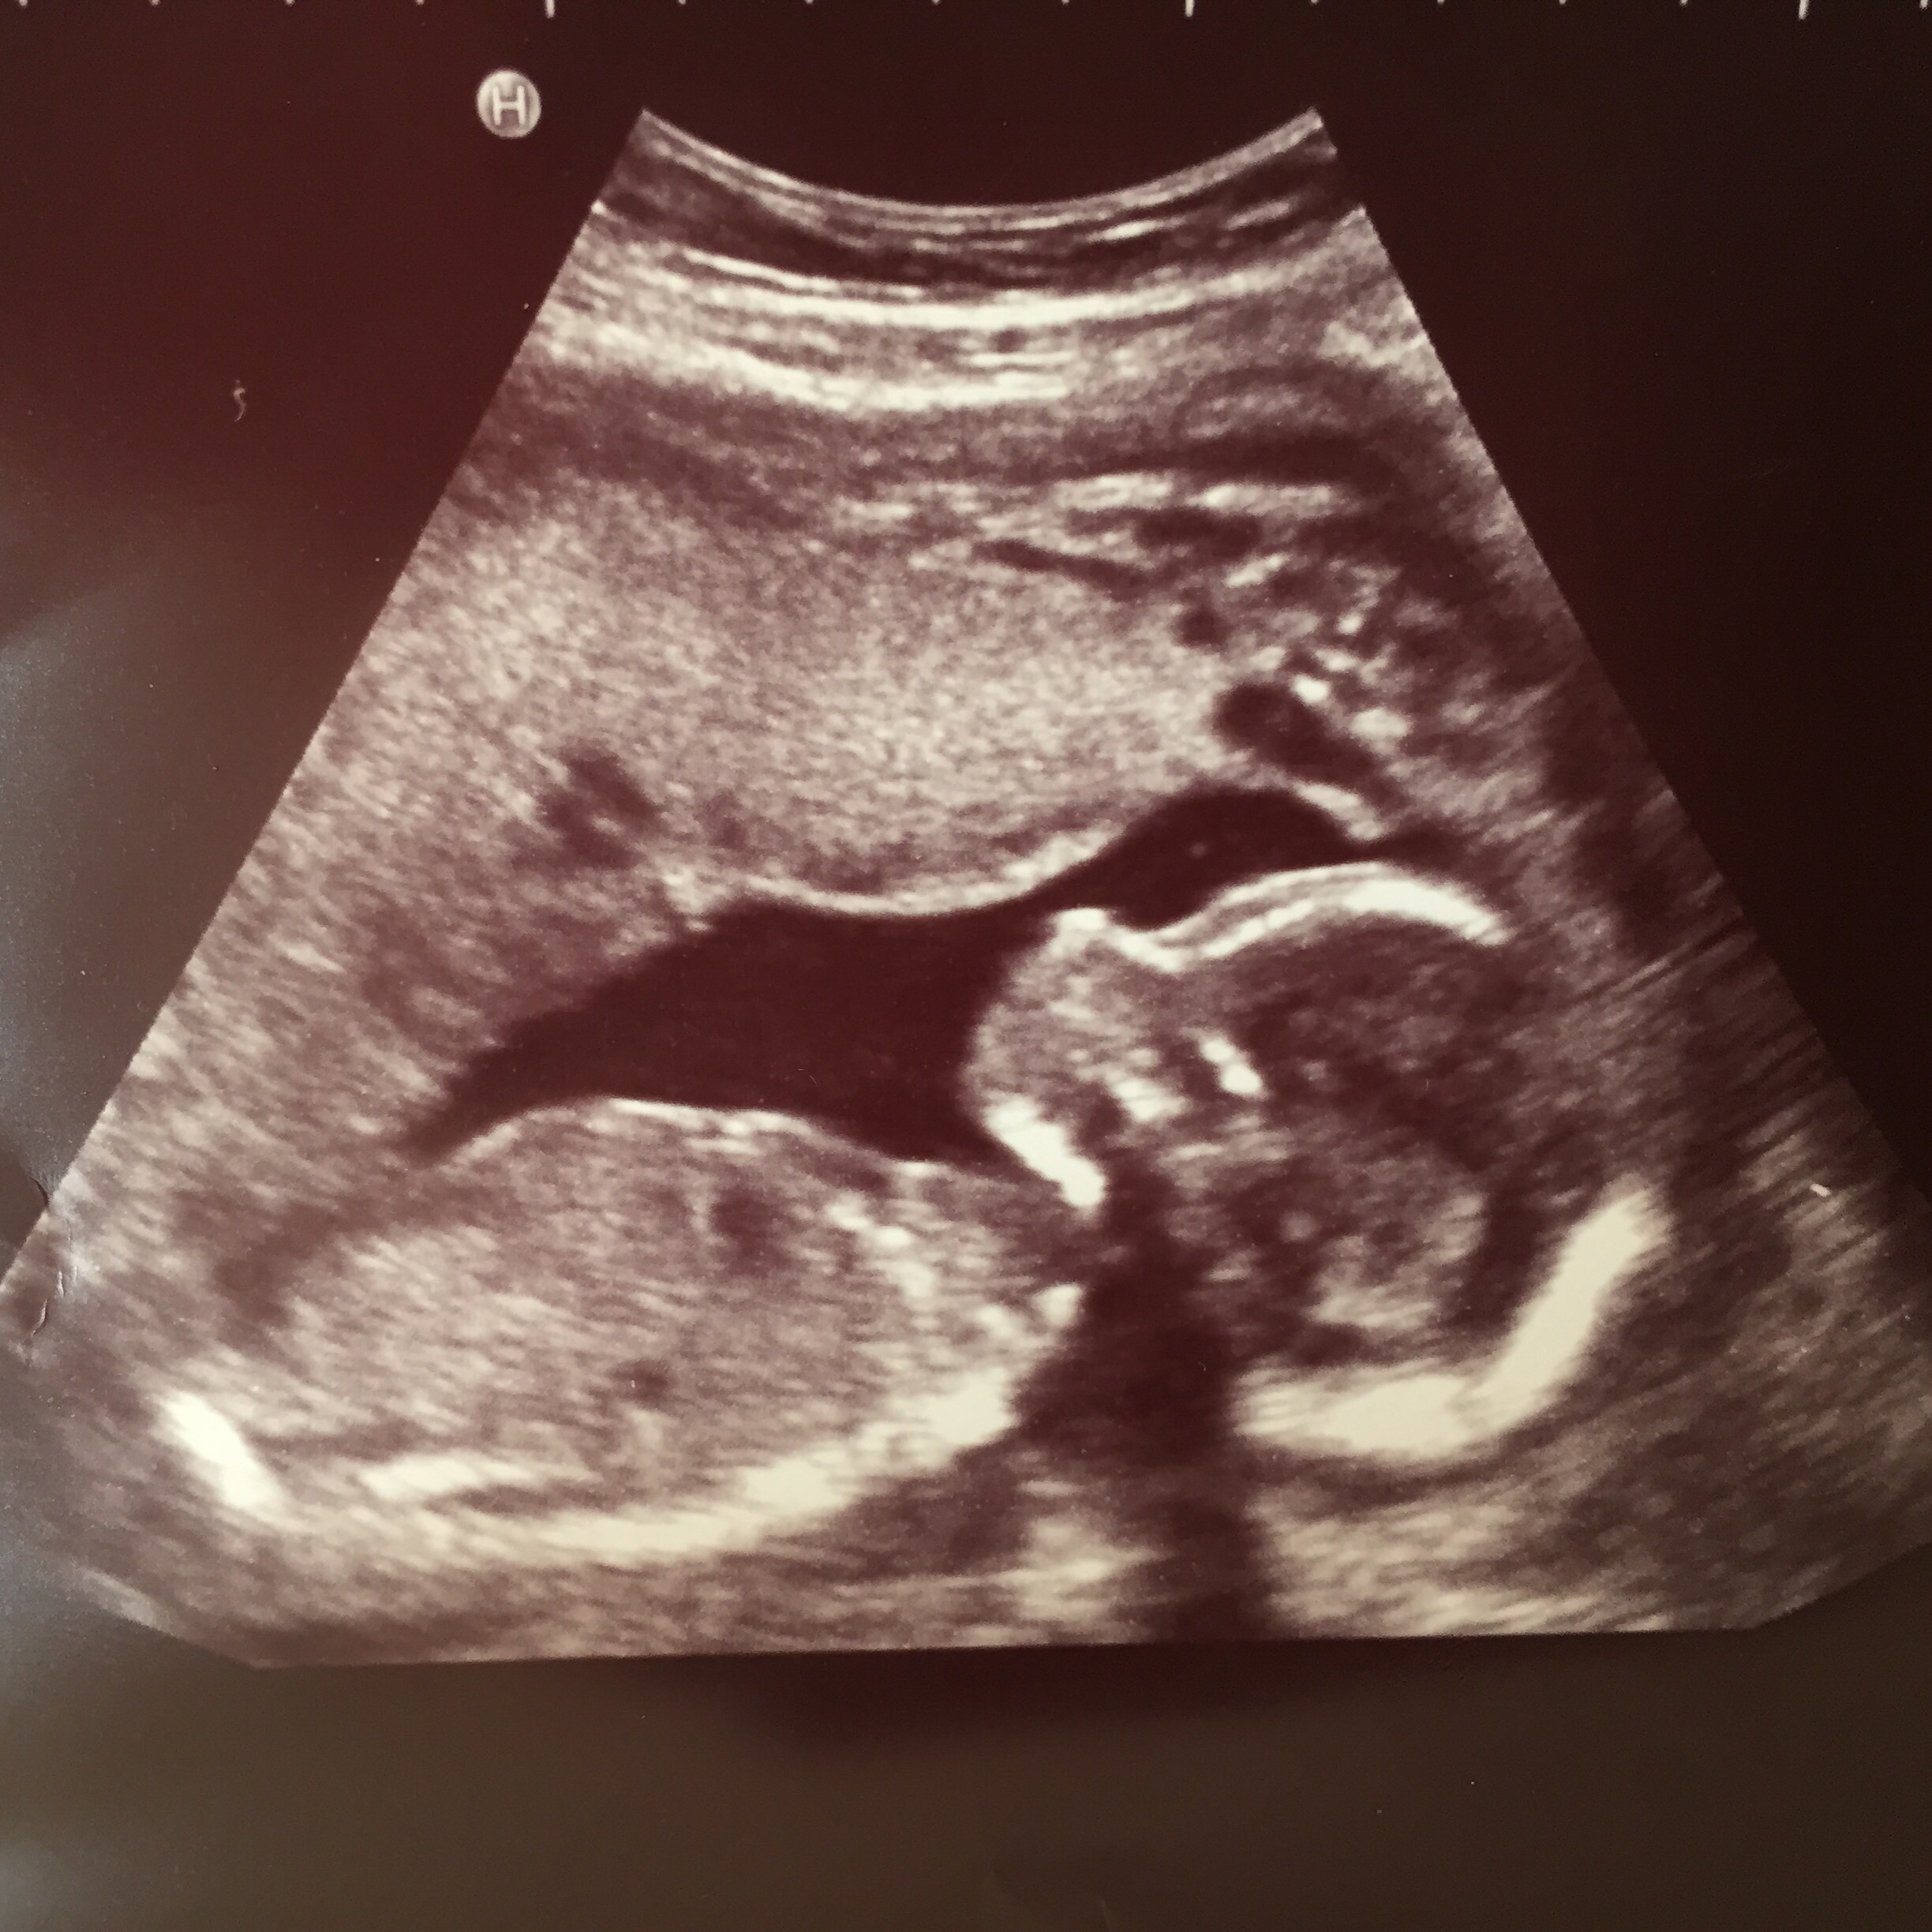

• 18w4d haven't felt Anything but had my anatomy scan which showed placenta at the top - cushioning the kicks. I saw her kick and love a lot but My baby is kicking that which is why I can't feel them until they're stronger so don't stress!

19 weeks today and I haven't felt anything that I'm aware of. FTM so I have no idea if I've been feeling her or not. It's probably still early. I have my anatomy scan on Thursday which I'm excited and scared about. At my last apt my doctor was having a hard time getting her heart beat because she was kicking and punching all around...she even asked if I could feel anything yet and I said no. I'm sure once it happens I'll know. I can't wait but at the same time having a living thing growing inside me still does freak me out. It'll happen soon enough.